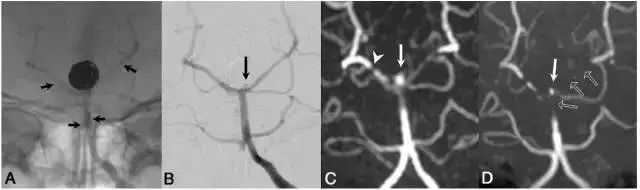

图1. 病例1:53岁,女性。A:Y型支架辅助的弹簧圈栓塞治疗,右侧PCA使用Neuroform支架,左侧PCA使用Enterprise支架,短箭头显示支架边缘;B. DSA图像,长箭头显示了颈部残留;C. Silent MRA图像,在支架短课件少量信号丢失,其中右侧PCA支架边缘出现较强的信号丢失(如白色小箭头所示);D. 同一天进行TOF-MRA检查,在基底动脉观察到较强的信号丢失,左侧PCA段可见完全的信号丢失(黑箭头),可见颈部残留(白箭头)